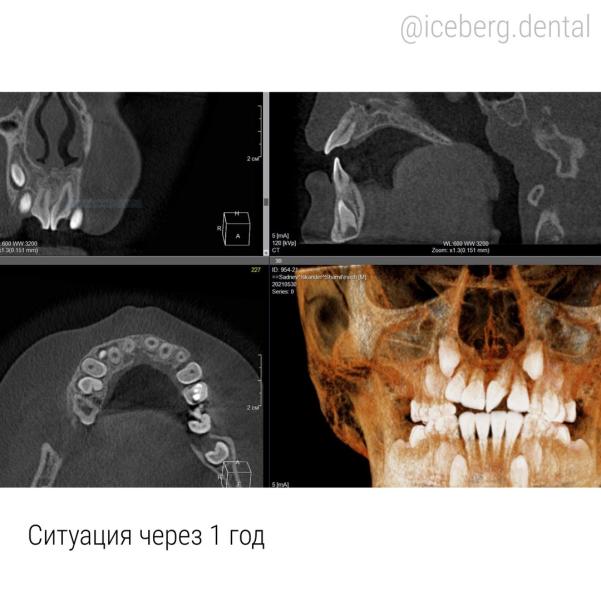

Какие результаты на сегодня и почему мы считаем их отличными?

✔️иногда после пересадки зуба возможна резорбция корня (его рассасывание, растворение), здесь этого не произошло, зуб отлично стоит.

✔️ВНИМАНИЕ! Нерв в зубе остался живым! Вы не ослышались — зуб действительно сохранен живым.

✔️есть медицинский нюанс, при таких манипуляциях выпиливается достаточно большой объем костной ткани и сложнее всего восстанавливается передняя стенка. Здесь восстановление прошло хорошо — стенка восстановлена.

✔️не смотря на то, что корень не вырос насколько это происходит естественным образом, подвижности нет, точнее подвижность идентична подвижности любого другого зуба.

Вы же знаете, что наши зубы держатся на связке, а не «намертво», поэтому есть показатель нормальной подвижности, т.е все тоже в порядке.